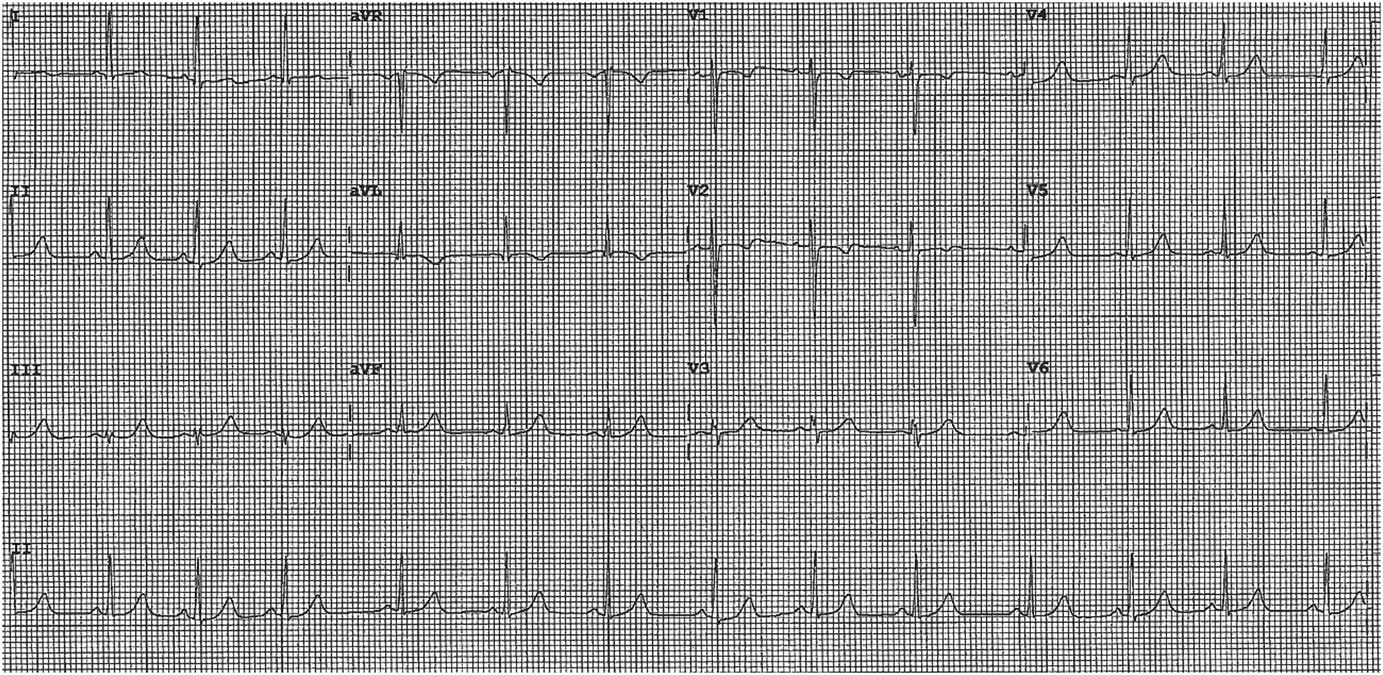

Subsequent to her referral, she had a recurrent episode of chest pain lasting 30 minutes. Her ECG at this time revealed dynamic 0.5-mm ST segment depressions in leads V2-V3 with T-wave inversion in leads V2 (Figure 2). She was subsequently transferred to the Coronary Care Unit.

Figure 2 ECG Subsequent to Referral.